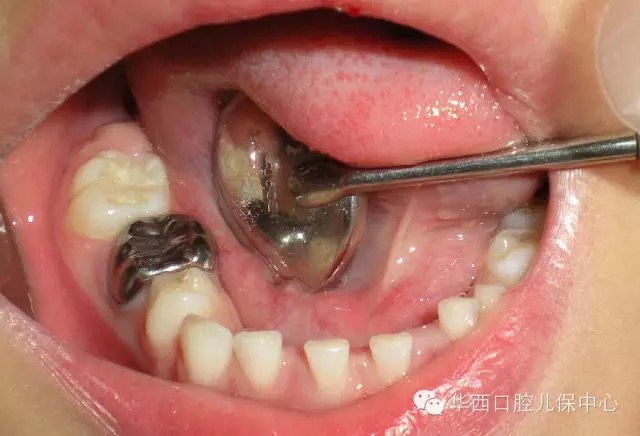

單個(gè)乳磨牙齲壞充填后的預(yù)成冠修復(fù)